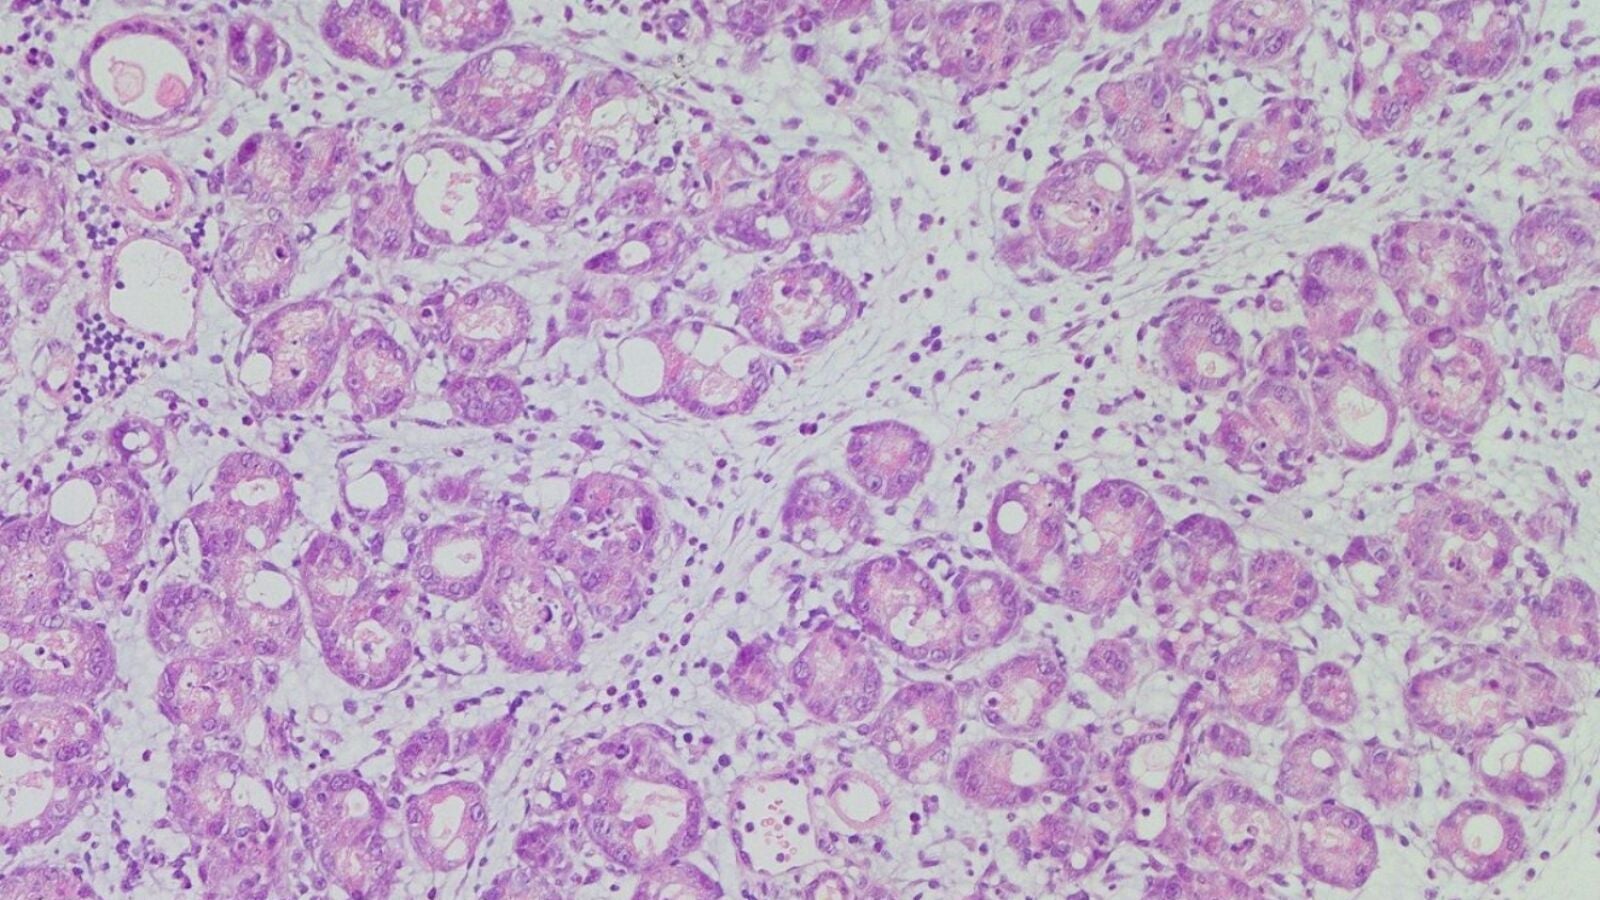

El páncreas, situado detrás del estómago, gestiona el suministro de energía de nuestro organismo. Lo hace segregando las proteínas (enzimas) responsables de que la glucosa, el principal combustible del cuerpo, llegue a otros órganos en el momento y cantidad necesarios. Estas proteínas se generan en las llamadas células acinares, que constituyen el 85% del páncreas y cuyo funcionamiento preciso aún está en investigación.

Los investigadores han descubierto que una molécula llamada NFIC es clave para el correcto funcionamiento de las células acinares. Este hallazgo ayudará a entender qué ocurre cuando los procesos normales fallan y se originan el cáncer u otras lesiones.

"Las células acinares son grandes factorías de proteínas", explica Real. "En nuestro laboratorio nos interesa saber cómo trabajan, porque cuando su función se perturba se favorece el progreso del tumor. El descubrimiento del papel de NFIC supone un paso más en el conocimiento de cómo las células del páncreas evitan mecanismos alternativos a su funcionamiento normal, que puedan favorecer el desarrollo del cáncer".

En la publicación explican que, si se desactiva NFIC, las células acinares no maduran correctamente, y el páncreas responde peor al daño y se vuelve más propenso a iniciar la formación de tumores.